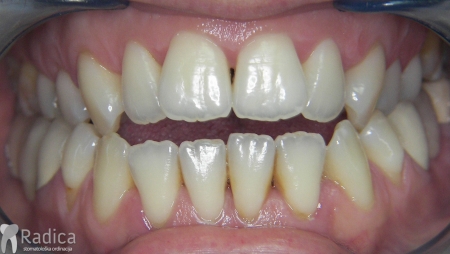

U galeriji slika su prikazani klinički slučajevi ovakvih odraslih pacijenta bilo da se radi samo o ortodontskoj terapiji ili predprotetskoj ortodonciji.